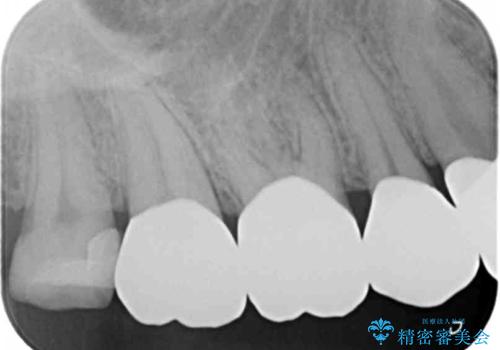

- 重度の歯ぎしり癖で歯がすり減り、見た目・噛み合わせの改善とこれ以上すり減る前の処置を希望され来院されました。

高さが短くなってしまった歯は、安定したクラウンを作るのが難しいため歯ぐきを下げる歯周外科を行ったのちに強度に優れるフルジルコニアクラウンで補綴治療を行います。

すり減ってしまった歯に対し、歯冠長延長術(歯周外科)を行うことで安定したクラウンを製作・装着することが出来ました。